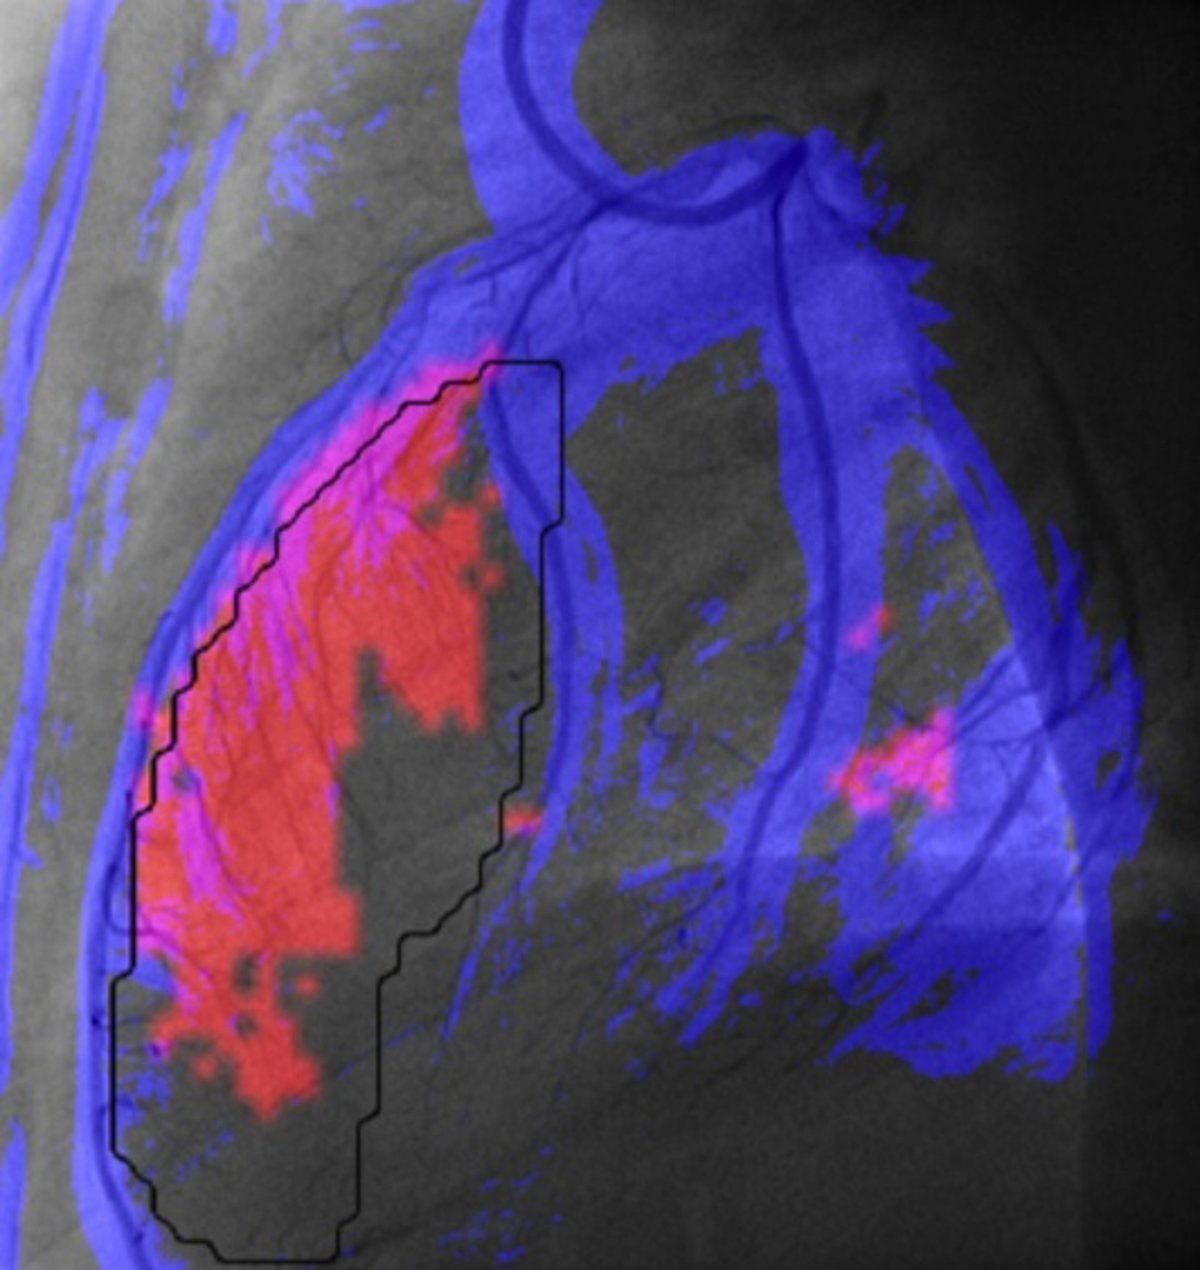

Investigadores del Centro de Visión para Computador (CVC) de la Universitat Autònoma de Barcelona (UAB) han diseñado una herramienta informática para mejorar y agilizar el diagnóstico de daño cardíaco después de sufrir un infarto.

A través del análisis de imágenes, la herramienta permite obtener una medida "cuantitativa, reproducible y más objetiva" de la irrigación miocárdica; identifica las regiones con menor riego sanguíneo, y facilita la comparación rápida entre los estados de antes y después de la operación, y entre dos arterias.